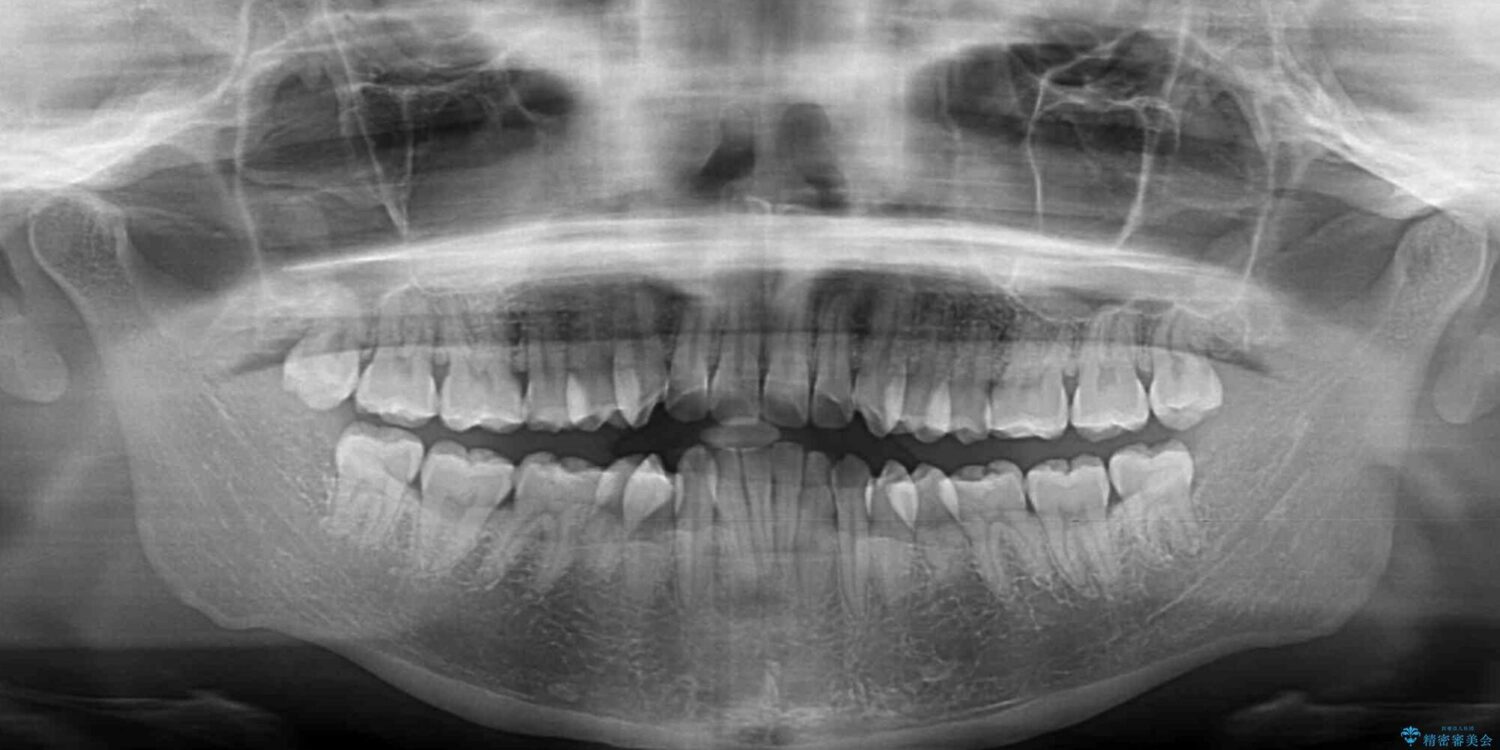

下唇が突き出るような口元の突出感が気になるとのことで来院された患者様です。

治療計画

上下顎ともに前突した歯列であったので、上下ともに左右の第1小臼歯4本を抜歯し、ワイヤー装置にて矯正治療を行うこととしました。

治療後について

抜歯スペースに前歯を移動させることで歯の突出感が改善され、非常に唇が閉じやすい仕上がりとなりました。